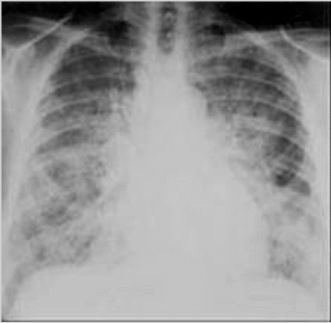

36. 40 歲女性病人,有貧血病史,二年前因生產後大出血,在大量輸血時發生 呼吸衰竭住院治療過。病人今日因嚴重貧血經門診轉入急診輸血,呼吸 12 次/min,SpO2 98%,心跳 102 次/min,血壓 102/60 mmHg,聽診心音和呼 吸音正常。在急診以 60 ml/h 流速靜脈輸入濃縮紅血球(packed RBC)。半小時後,病人開始抱怨呼吸困難。胸部 X 光檢查如圖示,下列的評估或處 置,何者較適當? (A)立即調整輸血速率,降低至原來流速的一半。 (B)此病人為心因性肺水腫,多於輸血四小時內發生,需在急診留 觀 。 (C)此病人的病況癒後差,死亡率高,應立即插管住院。 (D)此病人不適合使用大量利尿劑,如 Lasix。 (E)此病人不適合使用吸入性的氣管擴張劑和腎上腺素治療。